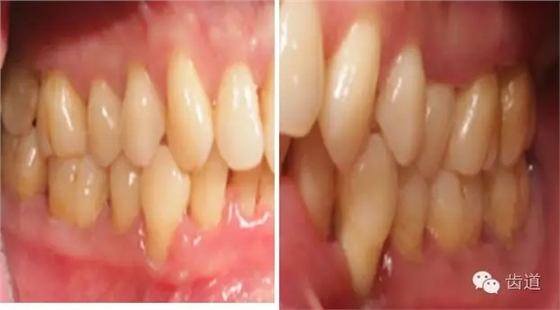

1、口腔衛(wèi)生狀況及局部刺激物(牙菌斑、牙石,不良修復體)

牙石及不良修復體

2、牙齦

(顏色、形狀、質地、退縮、BOP、PD、附著齦)